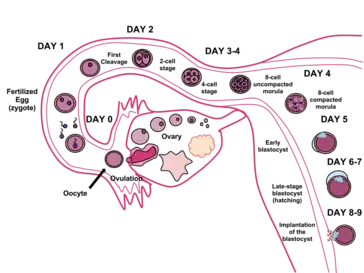

Human reproduction usually involves internal fertilization by sexual intercourse. In this process, the male inserts his penis into the female's vagina and ejaculates semen, which contains sperm. A small proportion of the sperm pass through the cervix into the uterus, and then into the fallopian tubes for fertilization of the ovum. Only one sperm is required to fertilize the ovum. Upon successful fertilization, the fertilized ovum, or zygote, travels out of the fallopian tube and into the uterus, where it implants in the uterine wall. This marks the beginning of gestation, better known as pregnancy, which continues for around nine months as the fetus develops. When the fetus has developed to a certain point, pregnancy is concluded with childbirth, involving labor. During labor, the muscles of the uterus contract and the cervix dilates over the course of hours, and the baby passes out of the vagina. Human infants are completely dependent on their caregivers, and require high levels of parental care. Infants rely on their caregivers for comfort, cleanliness, and food. Food may be provided by breastfeeding or formula feeding.[1]

Approximately every 28 days, the pituitary gland releases a hormone that stimulates some of the ova to develop and grow. One ovum is released and it passes through the fallopian tube into the uterus. Hormones produced by the ovaries prepare the uterus to receive the ovum. The lining of the uterus, called the endometrium, and unfertilized ova are shed each cycle through the process of menstruation. If the ovum is fertilized by sperm, it attaches to the endometrium and the fetus develops.